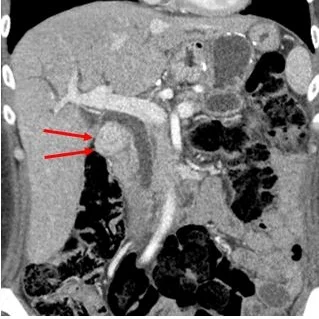

Conventional CT: Large mass (red arrows) in the porta hepatis. Note gastric bypass, biliary dilatation is chronic.